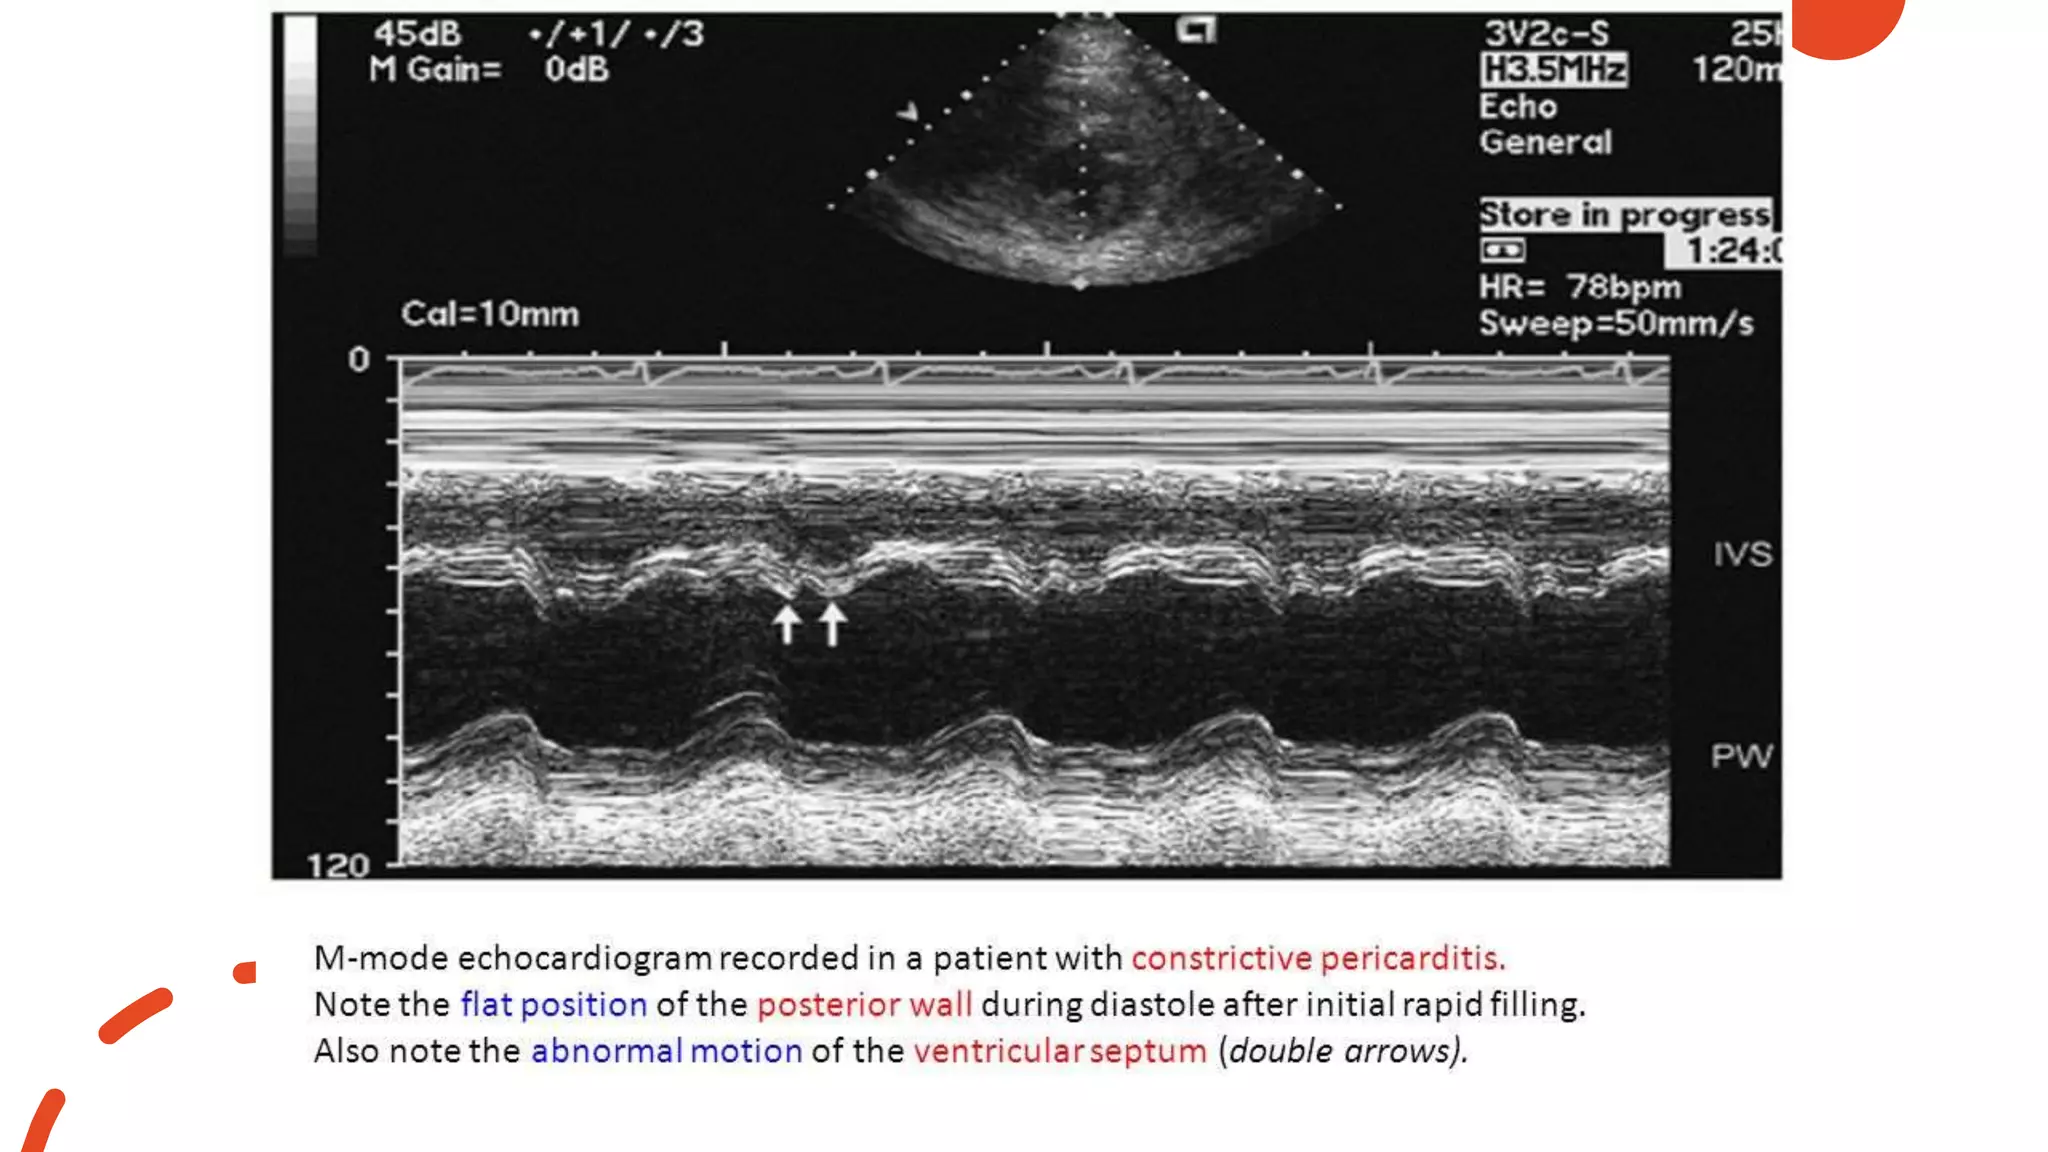

Constrictive pericarditis • Pericardial thickening •Paradoxical septal motion • Septal bounce ( abrupt displacement of the IVS during early diastole) • Flattening of mid & late diastolic motion of the posterior LV wall • Rapid early diastolic, or E-F slope of the mitral valve • Rapid downward motion of the posterior aortic wall in early diastole • Premature opening of pulmonary valve • Dilated IVC with blunted respiratory changes

pericarditis

• Paradoxical septal motion

• Septal bounce ( abrupt displacement of the

IVS during early diastole)

• Flattening of mid & late diastolic motion of the

posterior LV wall

• Rapid early diastolic, or E-F slope of the mitral

valve

• Rapid downward motion of the posterior aortic

wall in early diastole

• Premature opening of pulmonary valve

• Dilated IVC with blunted respiratory changes